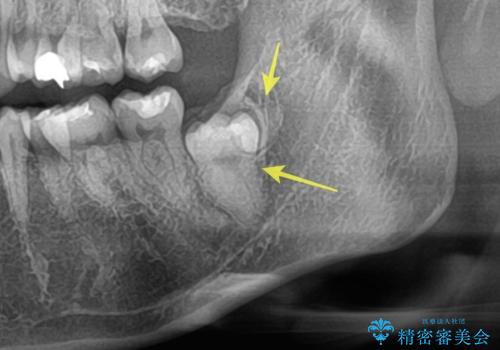

【埋伏智歯と埋伏智歯の過剰歯の抜歯】埋まっている親知らず2本の抜歯

担当医 河野豊嘉